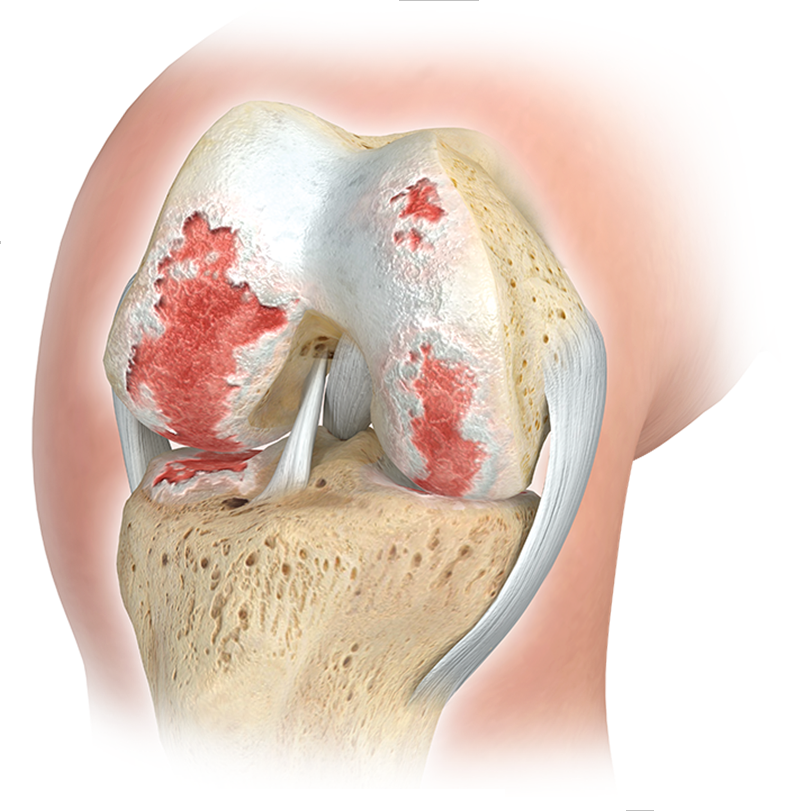

ARTROSIS DE RODILLA

DEBIDO al alto nivel de estrés al que están expuestas las articulaciones de la rodilla, a menudo se producen signos de desgaste a lo largo de la vida, lo que provoca importantes molestias y restricciones en la calidad de vida. Las lesiones deportivas tempranas, las desalineaciones o la obesidad favorecen significativamente este desarrollo.

COMO PARTE DE LA TERAPIA DE LA ARTROSIS DE RODILLA (artrosis de rodilla), TAMBIÉN PUEDEN SER NECESARIOS INTERVENCIONES QUIRÚRGICAS ADEMÁS DE MEDIDAS CONSERVADORAS:

- OPERACIONES ENDOPROTESICAS EN LA ARTICULACIÓN DE LA RODILLA (REEMPLAZO DE LAS PARTES DESTRUIDAS DE LA ARTICULACIÓN POR IMPLANTES ARTIFICIALES DE METAL Y PLÁSTICO ALTAMENTE RETICULADO).